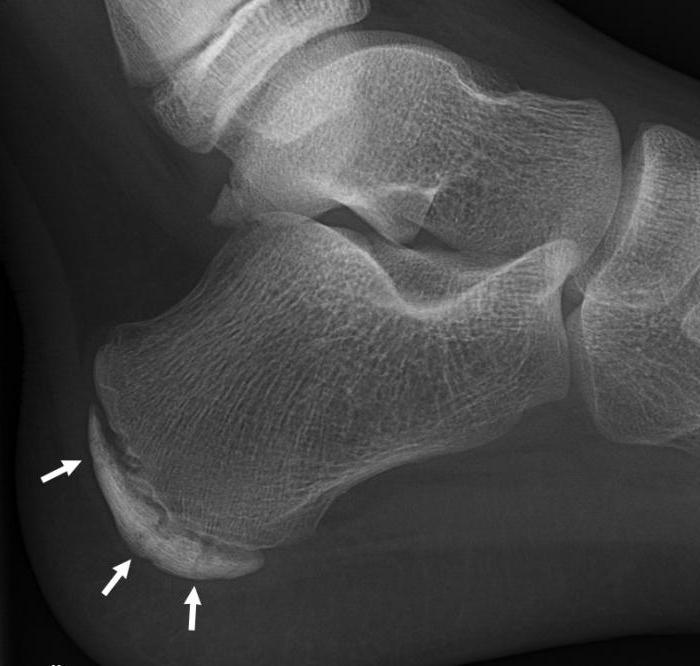

Необходимые исследования при болезни Шинца назначаются ортопедом или травматологом. Наиболее значимым диагностическим критерием является рентгенография, которая обязательно проводится в боковой проекции. Рентгенологические признаки на ранних и поздних стадиях таковы:

- ранние : кость пяточного бугра уплотненная, щель между ним и пяточной костью расширенная. Участок, на котором формируется новая костная ткань, выглядит пятнистым, что свидетельствует о неравномерной структуре ядра окостенения. В зоне видимости находятся рыхлые очаги верхнего костного слоя;

- поздние : пяточный бугор фрагментирован, есть признаки структурной перестройки и образования нового губчатого вещества кости.

В некоторых случаях результаты рентгена могут быть недостаточно точными (например, при наличии нескольких ядер окостенения). Тогда для уточнения диагноза назначаются дополнительные исследования – магнитно-резонансная или компьютерная томография.